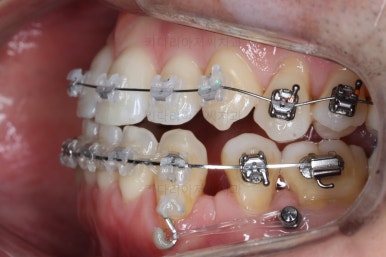

부산비수술교정 키다리아저씨치과에 처음 내원하셨을 당시의 입 안의 모습입니다.

아래 앞니에 결손치아가 하나 있네요. 송곳니-송곳니 사이에 앞니가 4개가 있어야 정상이지만 이 분은 3개에요. 의외로 아래앞니 하나 혹은 두개가 없는 경우가 굉장히 많답니다.

갯수가 맞지 않다보니 치열의 중앙도 맞지 않고 비대칭이 됩니다.

그리고 주걱턱이기 때문에 당연히 아랫니들도 앞으로 나올 수 밖에 없어 윗니보다 앞에 나와있어요.

이를 반대교합이라고 합니다.

어금니의 맞물림도 연쇄적으로 몇 칸씩 밀려있는 양상이라 효율도 좋지 못하고 치아의 건강에도 좋지 못해요.

이 분의 경우에도 전반적으로 잇몸이 약해져있을 수 밖에 없어요. 보시면 아시겠지만 잇몸 퇴축이 심해서 치아들이 길쭉길쭉해 보이죠.

장치를 처음 부착했을 때의 입안 모습입니다.

아랫니가 해야될 작업이 많고 기간이 오래 걸리기 때문에 윗니는 최대한 늦게 장치를 부착하여 불편감을 최소화 하기로 했어요.

이번에 사용한 장치는 자가결찰 세라믹장치입니다. Empower clear(엠파워 클리어)라는 장치이고 흔히 많이들 알고계신 클리피씨와 동일한 유형의 장치에요.